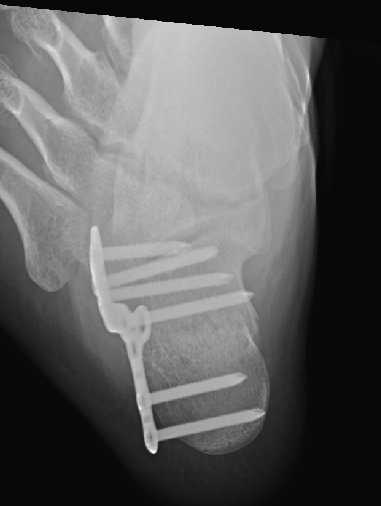

术后影像:

术中触及足部骨擦感,术后查足正侧位,发现跖骨骨折。